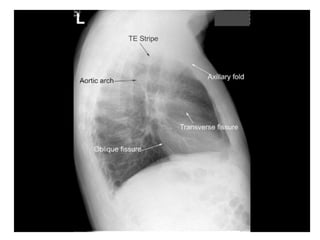

Lateral Film

Left Lateral

Right Lateral